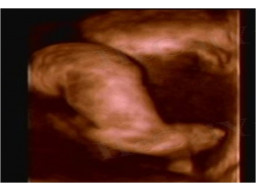

产科超声分正常与病理两大部分讲述。本章是正常产科超声部分的内容。

主要包括正常早孕声像表现、正常中晚孕声像表现。早孕中需要明确早孕的概念、早孕声像图表现及观察内容、早孕超声探测要点。中晚孕需要明确测量基本参数、切面、正常值,胎盘、羊水正常声像及测值、脐带解剖构成及正常声像表现。